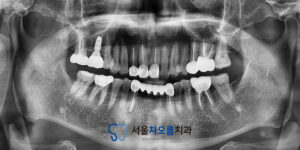

환자분과 상의 후, 상악(위턱) 치료부터

먼저 진행하기로 결정했습니다.

가장 우선적으로는 오른쪽 위 큰 어금니가

빠진 부위에 임플란트를 식립하였고,

임플란트가 뼈와 유착되는 몇 개월의

기간 동안 나머지 부위 치료를 병행하기로 했습니다.

임플란트 수술 후, 우선 왼쪽 위

충치가 심한 치아들에 신경치료를

진행하고 크라운 제작을 했습니다.

이어서 오른쪽 위 어금니에도

신경치료를 마무리하고 크라운을 제작했습니다.

상악 치료가 완료된 후에는 하악으로 넘어가,

왼쪽 아래 염증 부위 신경치료,

그리고 오른쪽 아래 큰 어금니는

온레이로 치료를 진행했습니다.

세마역임플란트 식립 부위는 충분한 기간 동안

유착이 잘 이루어졌고 마지막으로 임플란트

최종 보철물을 장착하면서 치료를

모두 마무리할 수 있었습니다.